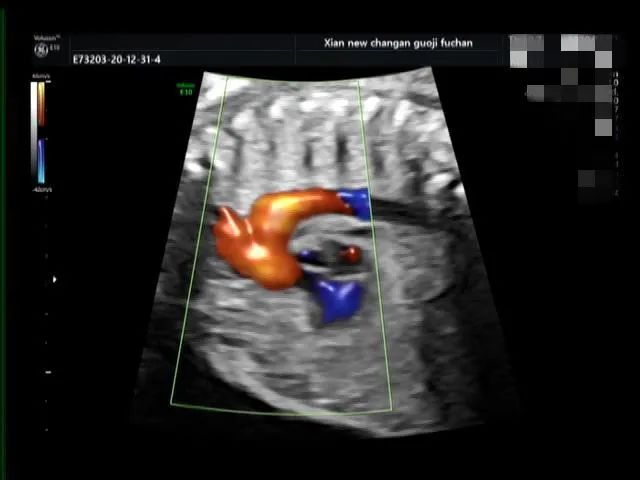

病例三

脐带打结

脐带打结是产科胎儿窒息的高危因素之一,利用产前超声检查能够提供准确有价值的诊断依据,我院自 2020 年 10 月至今共产前诊断处 4 例脐带打结。

产科医生向家属告知病情,因 4 例孕妇孕周都在 38W 以上,家属要求行剖宫产手术,娩出婴儿,Apgar 评分:10 分。外观无畸形,脐带中部近胎儿处见真性打结。

脐带真结较为少见,是脐带走形异常或脐带过长在宫内形成环套,胎儿活动穿越环套所致,往往引起不同程度的并发症,易引起胎儿宫内窘迫,严重者可致胎死宫内。

产前超声如怀疑脐带打结,需高度重视,孕期加强监护,注意可疑处脐动脉及脐静脉内径及血流动力学变化,3D 彩色多普勒高分辨仿真血流技术可立体、直观显示脐带形态结构及血流,对脐带打结有一定的诊断价值。